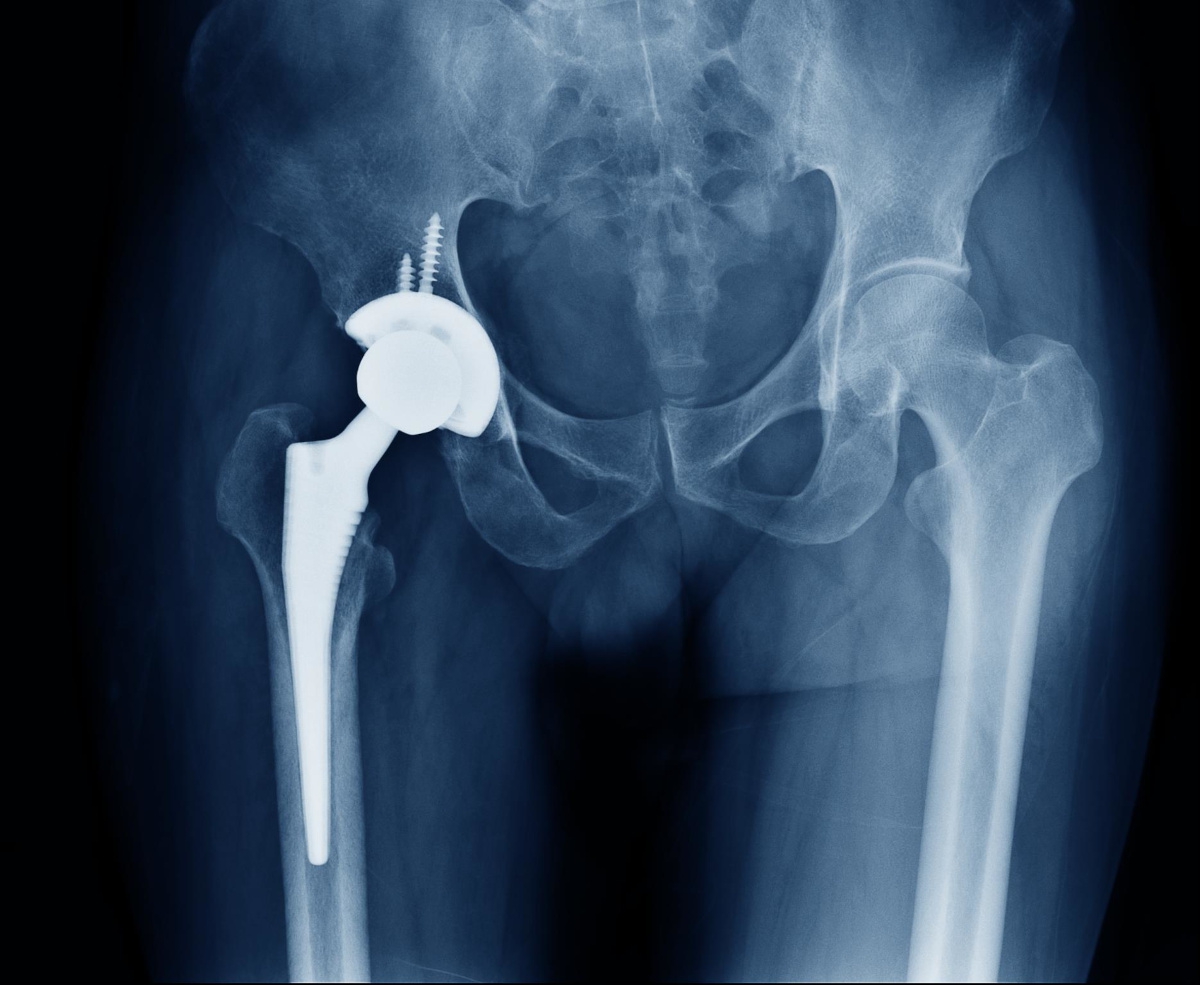

Kalça Protezi

Kalça Protezi orta yaştan sonra yapılan bir ameliyattır. Bu ameliyat için üst sınır bir yaş yoktur. Endikasyonuna göre de kemik gelişimini tamamla...

Robotik Kalça Protezi Ameliyatı

Robotik kalça protezi ameliyatı, son yıllarda geliştirilen bir teknoloji ile gerçekleştirilen bir cerrahi yöntemdir. Bu ameliyat, kalça protezi ame...